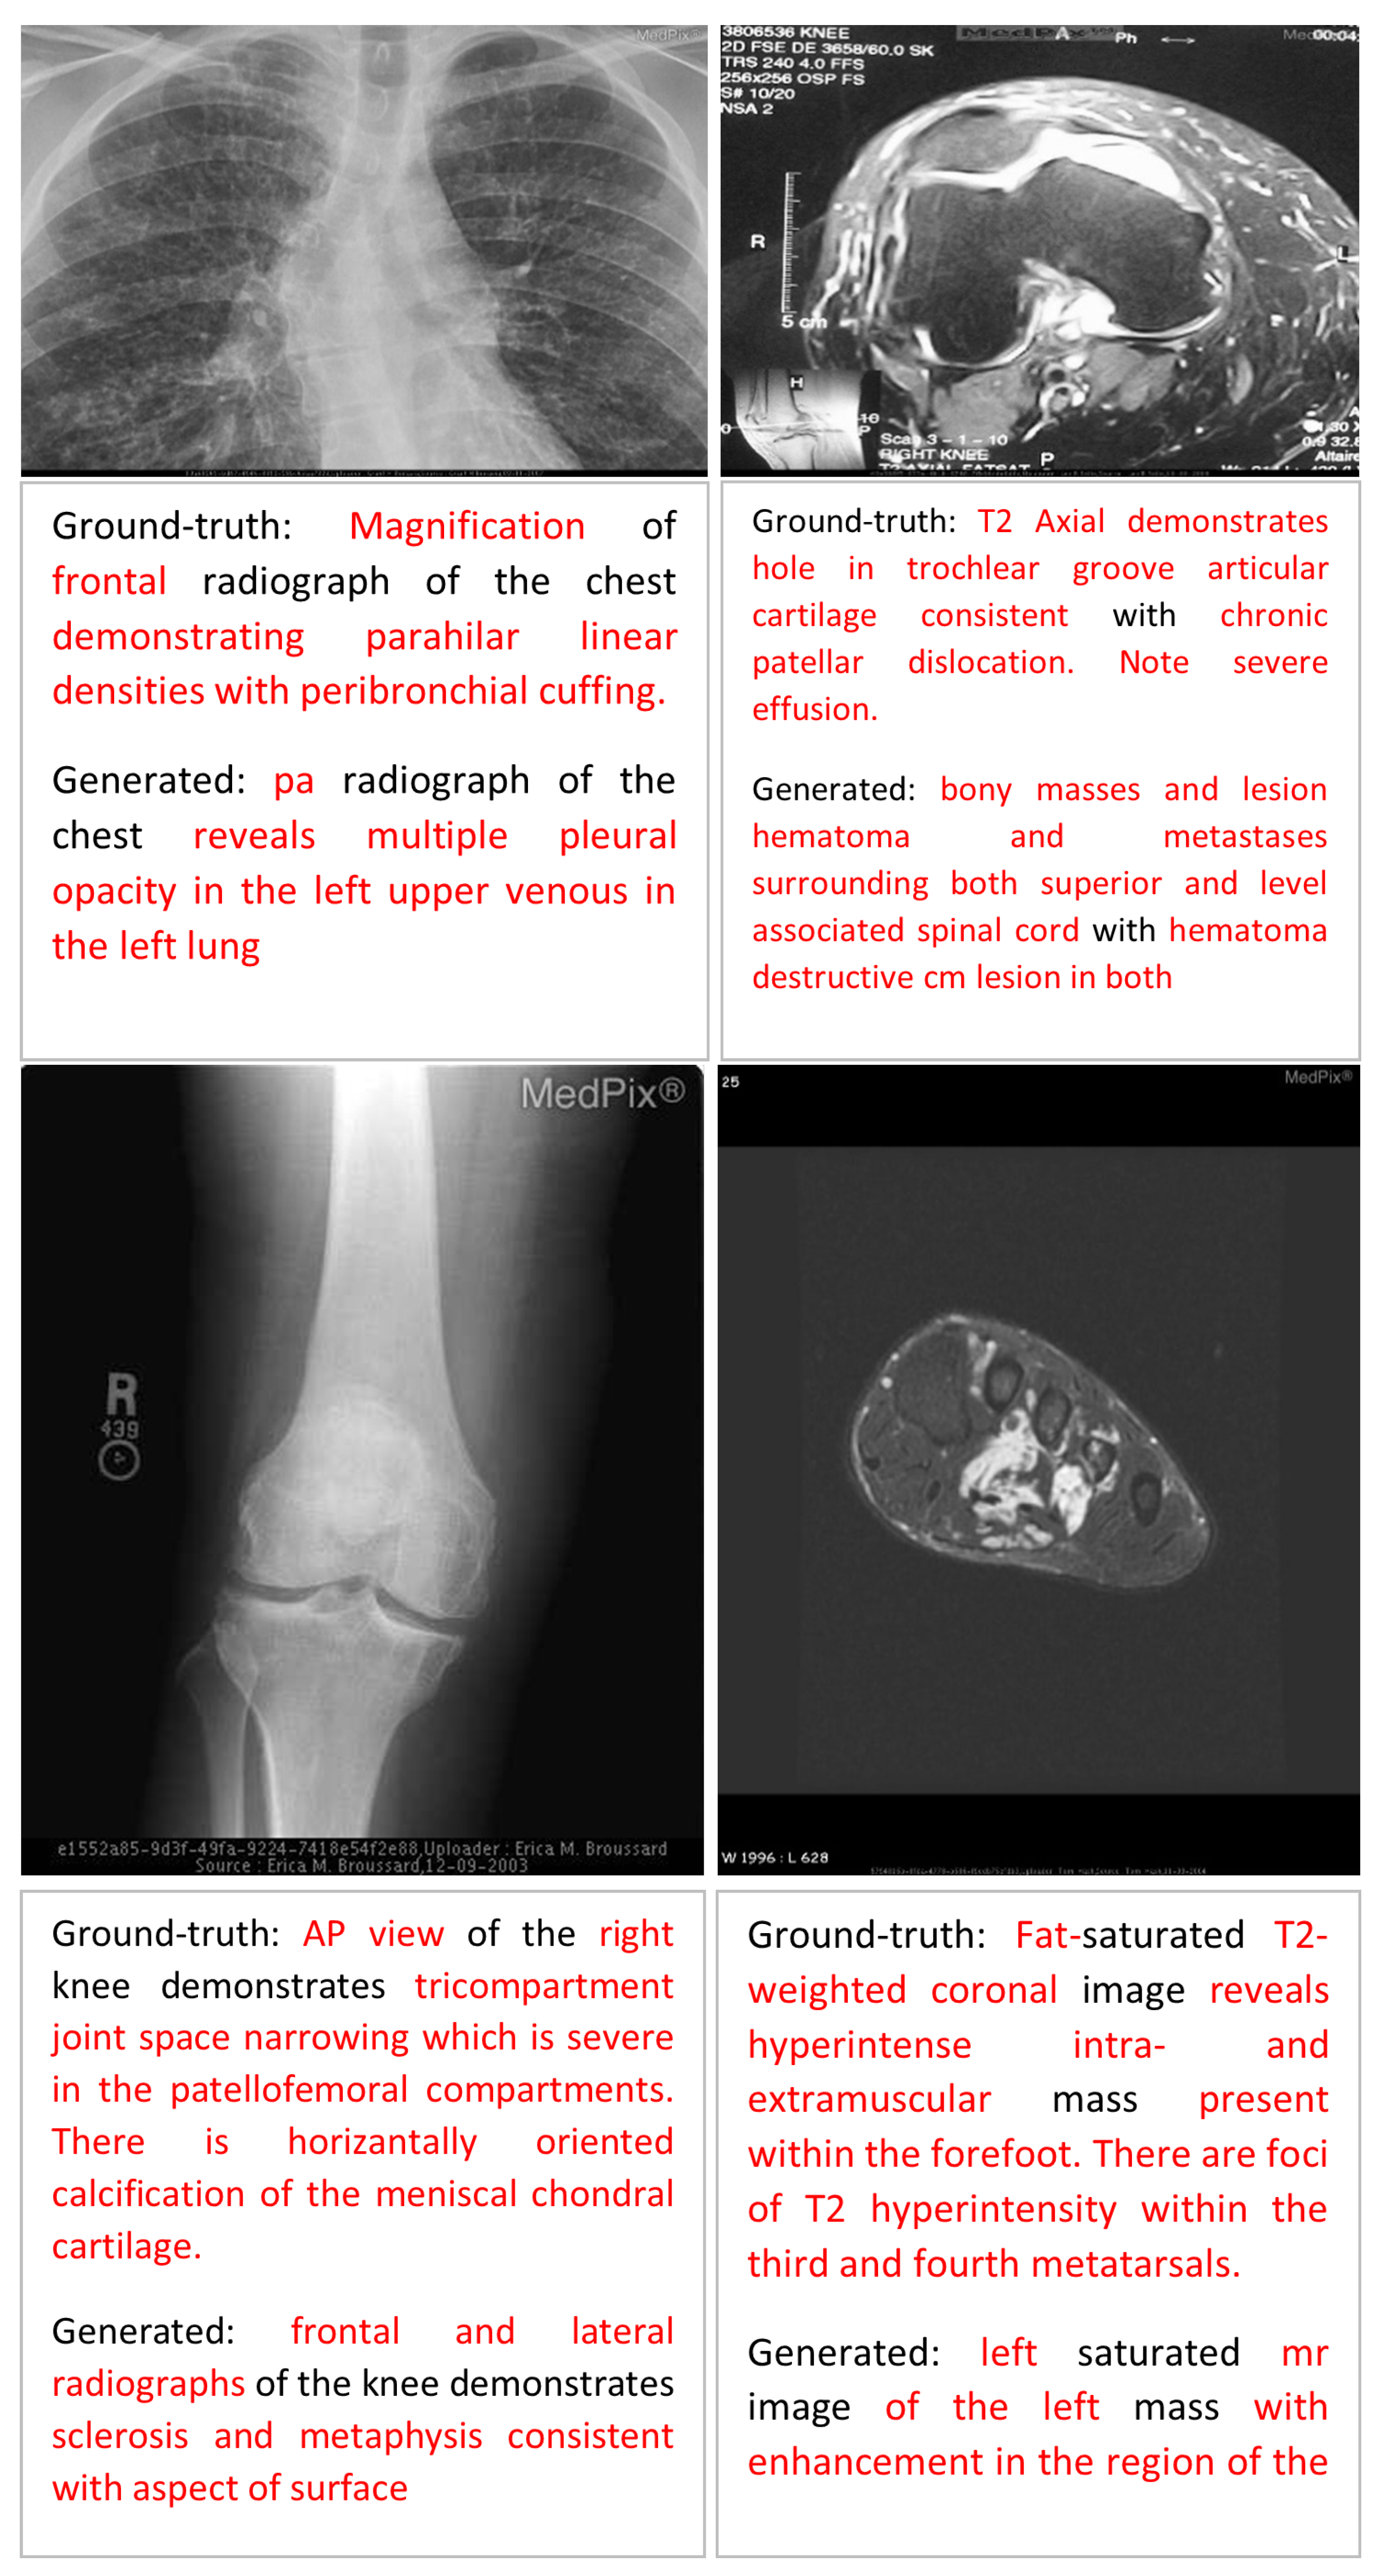

Error Analysis